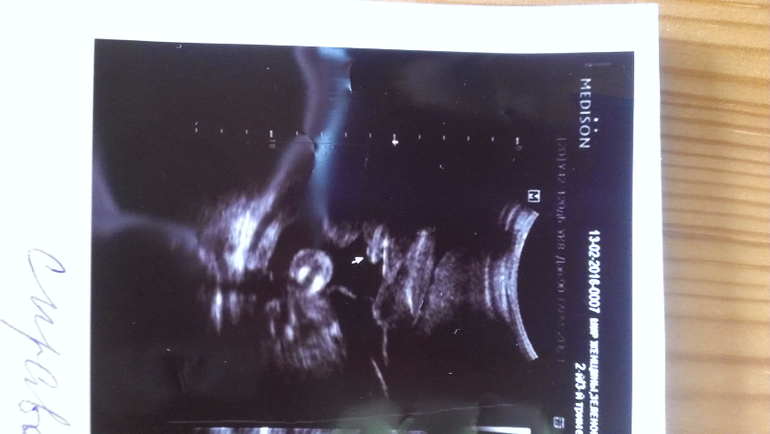

Внутриутробное развитие двойни/тройниНа узи в 20 недель уверенно сказали - два мальчика и на снимках так четко выделили, а неделю назад в другом центре врач как раз не очень уверенно, но предположила, что обе девочки...

На узи в 20 недель:

А у вас ну очень похожи на пацанов)

Вот мне тоже кажется, что, по крайней мере, с одним не могли ошибиться)) В любом случае, розовое (как и голубое) закупать не планировала, но люблю быть готовой.

Еще, все кто видел верхнее фото - сразу сказали, нос папин. Надеюсь, мальчику достался))